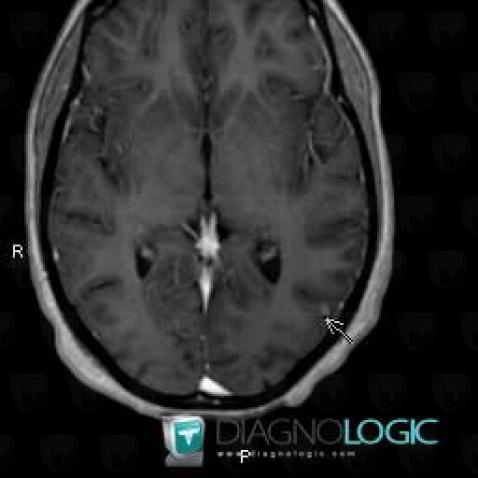

Voici les informations spécifiques à l'image clé ci dessus:

- Diagnostic Tuberculose (lié à Abcès), Localisation(s) Hémisphères cérébraux, comportant les gammes Lésion intracérébrale à réhaussement modéré

Voici les informations spécifiques à l'image clé ci dessus:

- Diagnostic Tuberculose (lié à Abcès), Localisation(s) Hémisphères cérébraux, comportant les gammes Lésion intracérébrale à réhaussement modéré